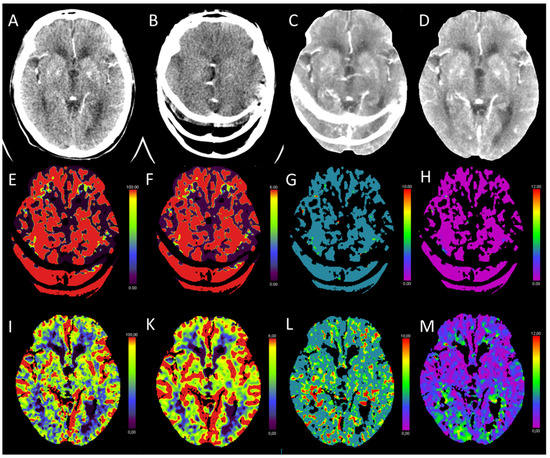

3.2. Acute Posterior Fossa Infarcts

3.3. Global Hypoxic-Ischemic Injury/Brain Death